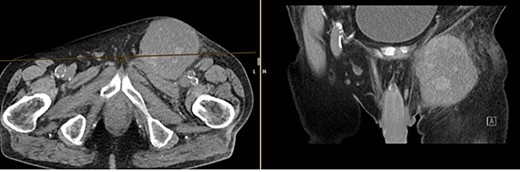

Further clarification was sought through a computed tomography (CT) scan of the entire abdomen (Fig. 1). The CT from 25 February 2022 showed an oval, encapsulated structure in the right groin area, most likely interpreted as a soft tissue hematoma. No active bleeding was observed. An enlarged lymph node was considered as a differential diagnosis. A follow-up CT on 1 August 2022 showed a size-progressive formation within the suspected right inguinal hernia compared with the previous examination in February (Fig. 2). There was no evidence of tumor recurrence or metastasis-suspect lesions intra-abdominally. A previous hysterectomy was also noted.

CT of the abdomen from 1 August 2022: size-progressive formation within the right inguinal hernia compared with the previous examination from 25 February 2022; no indication of tumor recurrence or metastasis-suspect lesions intra-abdominally, post-hysterectomy.